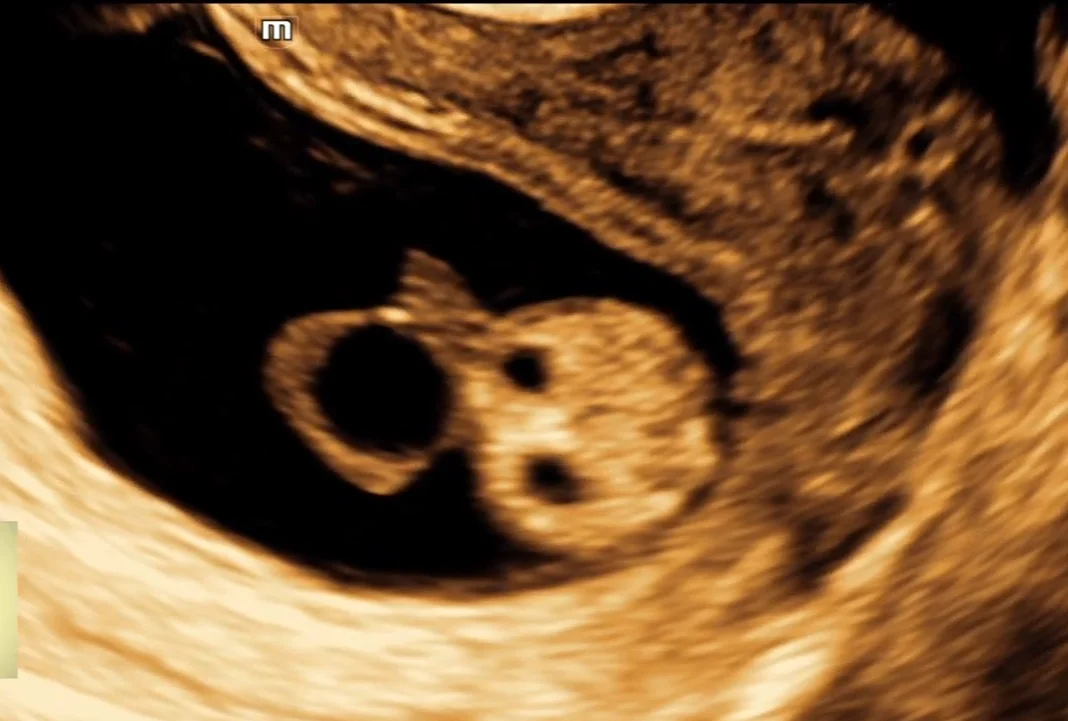

• Thai 5 tuần

• Thai 5,5 tuần: Yolk sac

• Thai 6-6,5 tuần

• Thai 7 tuần

• Thai 7-8 tuần

• Siêu âm thai quý I bình thường